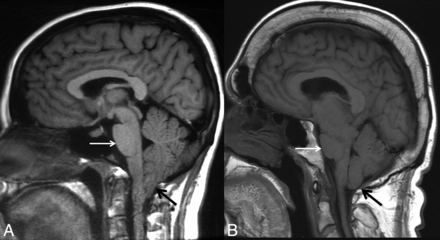

SIH can be mistaken for a Chiari type I malformation on imaging (Fig 1) due to the superficially similar radiologic appearance of cerebellar tonsillar descent.9 Although in some cases the differentiation can be challenging, there are several key imaging differences. In SIH, the tonsils usually maintain their normal shape rather than being inferiorly pointed and often do not descend more than 5 mm below the foramen magnum.22,23 In addition, the midbrain also descends in SIH, whereas it will maintain a normal position in Chiari type I. The superior aspect of the cerebral aqueduct (iter) may fall beneath the incisural line, which extends from the anterior tuberculum sellae to the inferior point of the venous confluence of the straight sinus, whereas it does not change position in Chiari type I.24,25 The presence of a syrinx will generally indicate a Chiari type I malformation, though there are rare reports of this developing in SIH.26 The subarachnoid spaces in the posterior fossa, foramen magnum, and normal ventricular caliber will be preserved in Chiari I malformations, whereas they will be effaced in SIH. Flattening of the pons is commonly seen with pronounced SIH-associated brain sag but will not be present with Chiari type I malformations, in which the prepontine cistern will be maintained. Finally, patients with a Chiari malformation will not exhibit diffuse dural enhancement.

Chiari type I malformation versus SIH. A, Sagittal T1WI demonstrates a Chiari type I malformation with descent of cerebellar tonsils 1.4 cm below the foramen magnum (black arrow). Note the typical “peglike” morphology. The prepontine cistern is preserved, and the pons maintains a rounded ventral morphology (white arrow). B, Sagittal T1WI in a patient with severe brain sag due to SIH shows mild descent of the cerebellar tonsils at the foramen magnum (black arrow), but with normal morphology. The pons is flattened (white arrow) with effacement of the prepontine cistern. There is also profound effacement of the subarachnoid spaces in the posterior fossa.